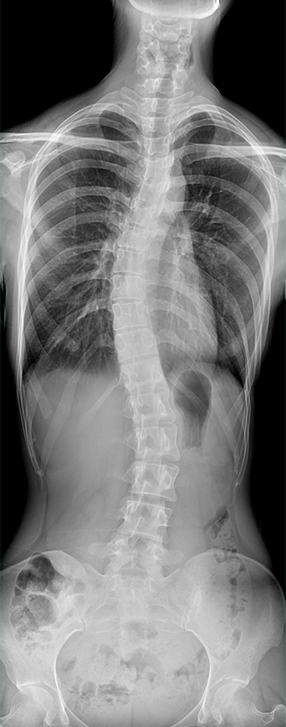

適用于全身各部位攝影

(常規攝影和特殊攝影)